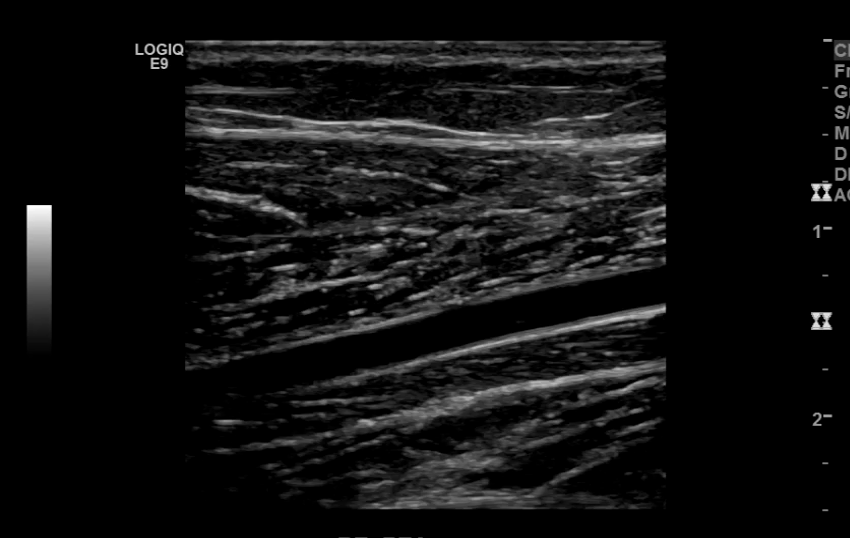

The iliac arteries bifurcate into external and internal iliac arteries (EIA and IIA). The EIA continues caudally turning into the common femoral artery (CFA) which further bifurcates into superficial femoral (SFA) and deep femoral artery (aka profunda femoris). The SFA then converts into the popliteal artery which bifurcates into the tibioperoneal trunk and anterior tibial artery (ATA). The tibioperoneal trunk bifurcates into posterior tibial artery (PTA) and the peroneal artery. The anterior tibial artery descends further to become the dorsalis pedis artery (DPA).

Anterior Tibial Artery